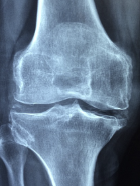

무릎 퇴행성관절염 증상 원인 관리방법 등 무릎 퇴행성관절염 정보에 대해 알아보도록 하겠습니다. 무릎 퇴행성 관절염은 무릎 관절을 보호하는 연골이 점차 손상되고 퇴화되면서 관절에 염증과 통증이 생기는 질환입니다.